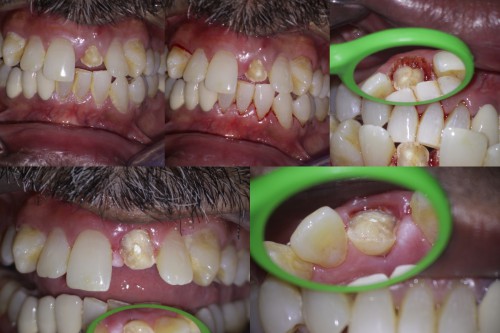

Pt 47 yoM reported after 10 days of trauma to his front teeth.  Clinical examination […]

Crown fracture extending sub-gingival

By Revathi Miglani / September 18, 2018

Pt 55 yoM presented with fracture of #9.  History of trauma 2 wks back and […]